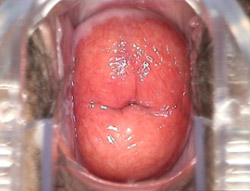

宫颈糜烂图

宫颈糜烂

中度宫颈糜烂